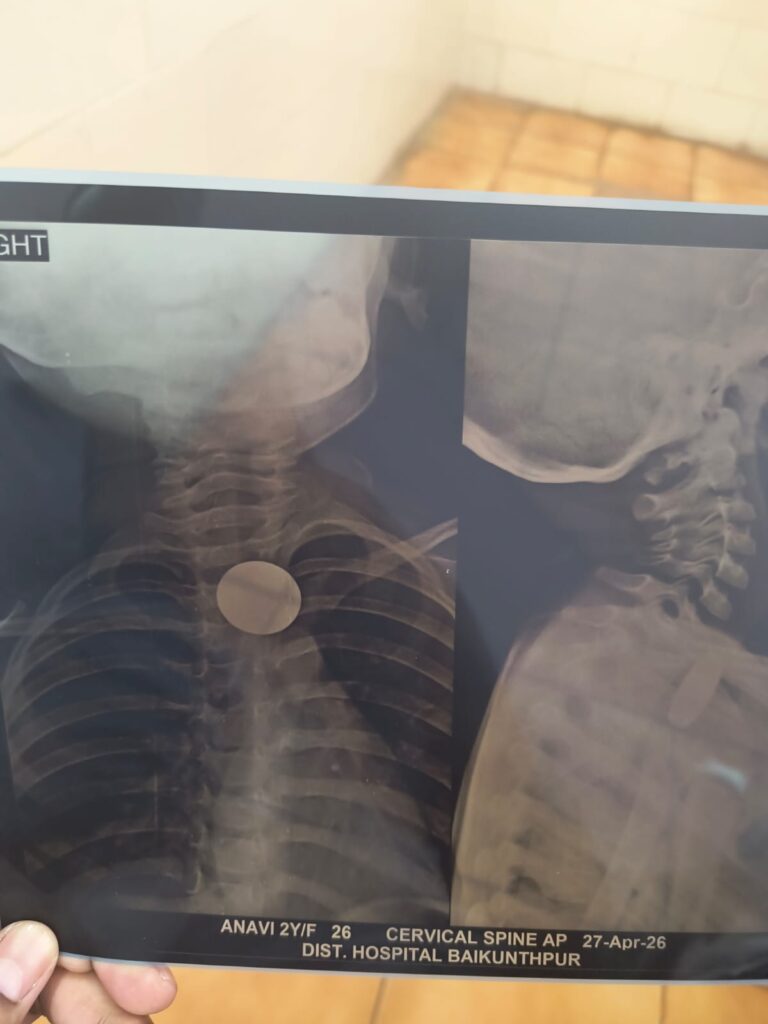

खेलते-खेलते सिक्का निगल गई 2 साल की बच्ची, डॉक्टर ने बचाई जान

एमसीबी जिले के नागपुर की रहने वाली 2 साल की मासूम बच्ची आनवी खेल-खेल में ही 5रुपए का सिक्का निगल गई। बच्ची जब सोमवार की दोपहर में उल्टी करने लगी तब माता-पिता समेत जब परिजनों इसको लेकर तत्काल बैकुंठपुर के जिला अस्पताल पहुॅचे। जहा पर सिविल सर्जन डॉ. आयुश जायसवाल के नेतृत्व में ईएनटी विशेषज्ञ डॉ. योगेश्वर चौहान ने बच्ची का एक्सरे कराया जहा पर उसके गले में सिक्का फंसे होने की पुष्टि होने के बाद उसके गले में फंसे सिक्के को बाहर निकाल लिया गया है उसकी हालत अब खतरे से बाहर है। बताया गया कि बच्ची को उल्टी हो रही थी गले के संवेदनशील हिस्से में सिक्का फंसा होने के कारण मासूम की स्थिति चौहान अभी तक लगभग एक दर्जन से अधिक बच्चों के गले से सिक्का निकालकर जाने बचा चुके हैं।